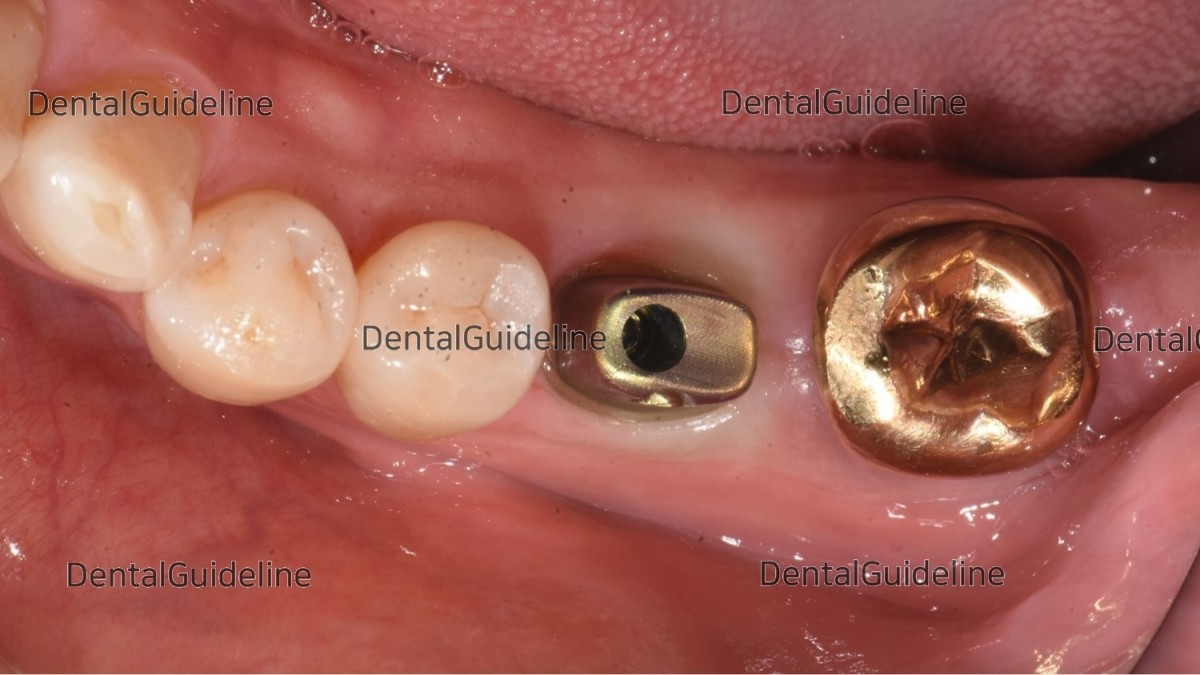

Intra-oral photo on the day of restoration.

A zirconia crown was seated by adjustment of contact and occlusal surface.

The crown was cemented and the access hole was filled with composite resin.